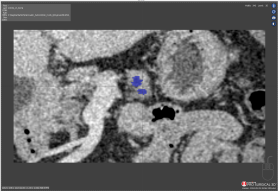

Scan 29: IOU of 6.7

Intersection Over Union (IOU)

IOU is the intersection of the area of the Ground truth and the test segmentation over the area of both the Ground truth and test segmentations.